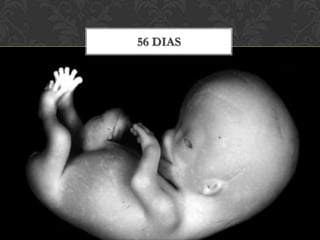

56 dias